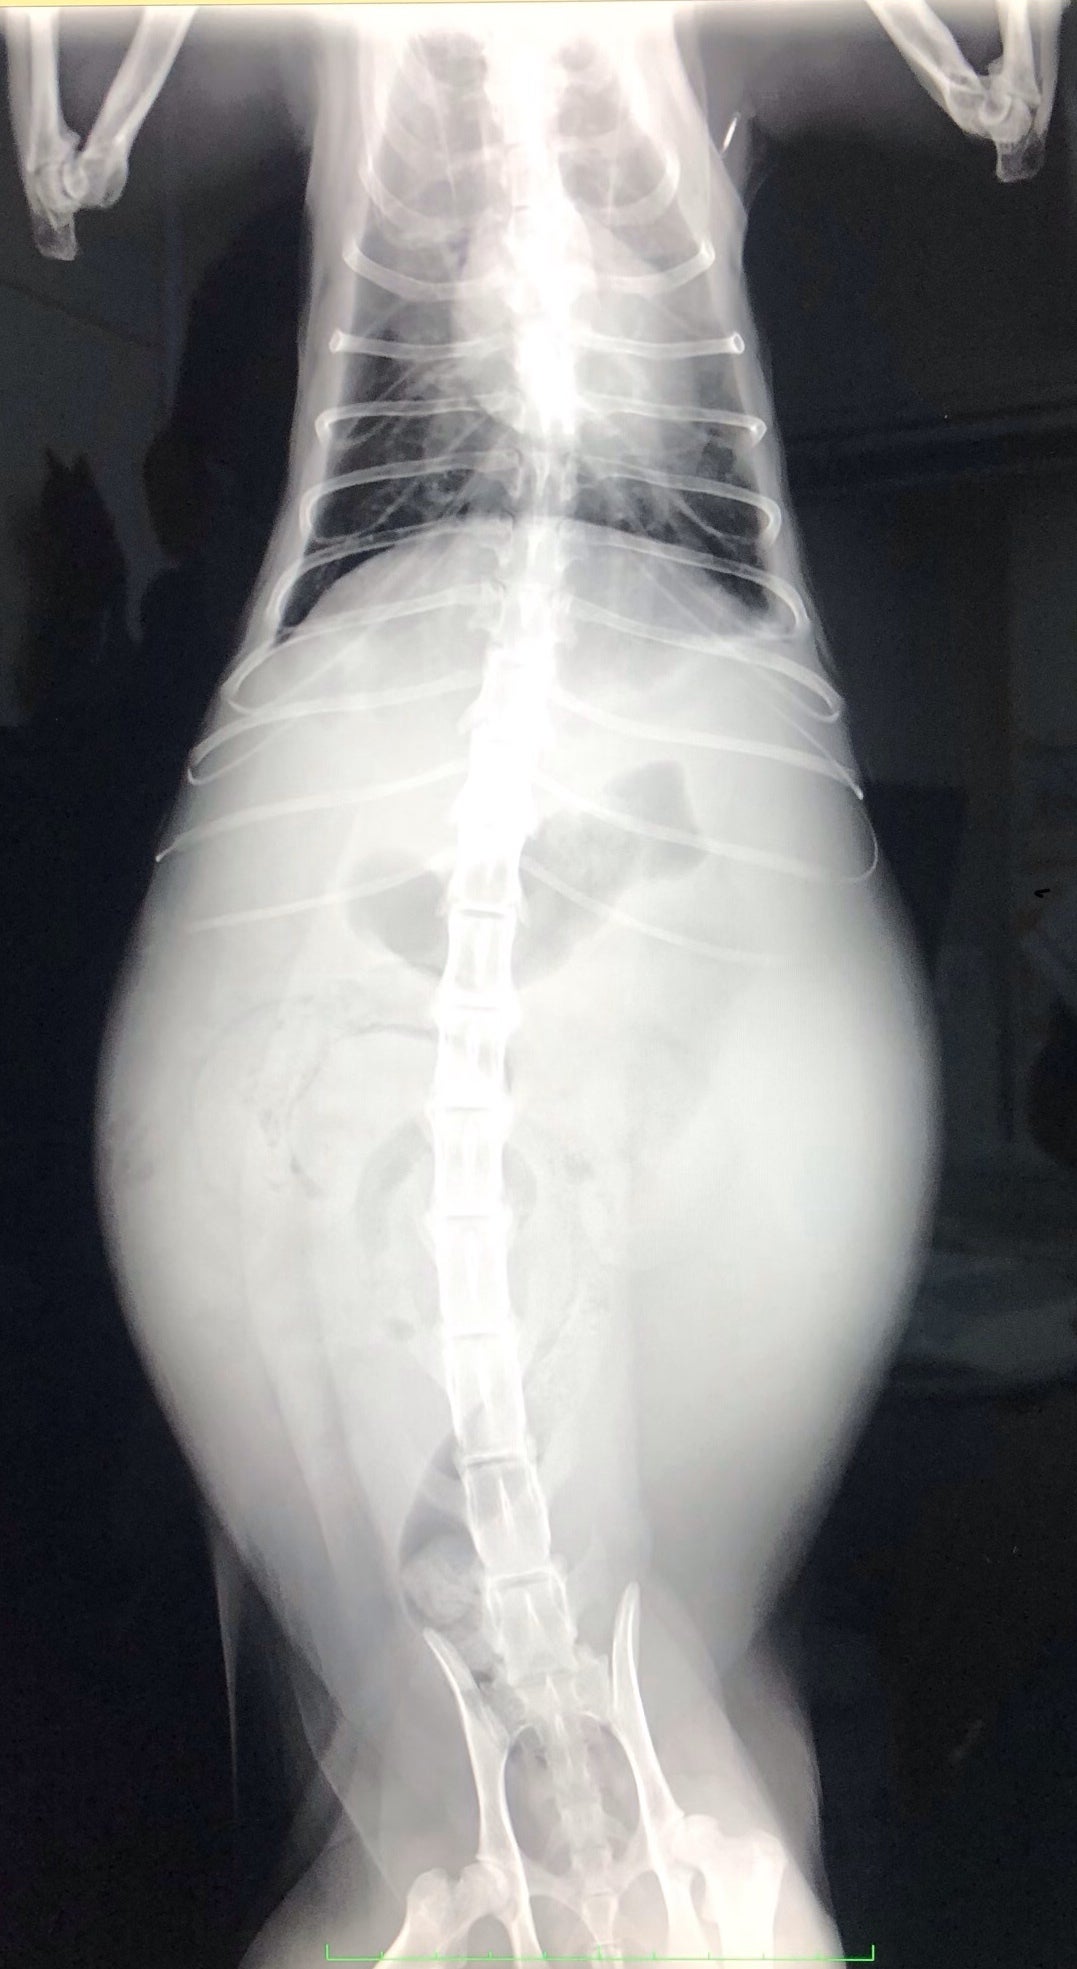

昨年6月の第一子の誕生の前に、ずら丸を家に迎え入れました。娘とも仲良く過ごしていましたが、突然のFIP疑診。ウェットタイプで腹水が溜まってしまい、まともに生活を送るのが困難な状態になってしまいました。今回の診断を機にこのプロジェクトを立ち上げています。

FIPという診断を受けた時に、あらゆる手段を使いこの病気について調べました。動物病院の先生やネットで調べた結果、外猫・野良猫のほとんどが持っているコロナウイルスが突然体内で変異し、FIPウイルスになるということが分かりました。FIPウイルスは一度発症してしまうと元に戻ることはありません。原因はストレスのことが多いと言われており、ずら丸にストレスを与えてしまっていたと日々嘆くばかりです。現在の症状としては腹水・胸水の貯留、食欲減退、便秘、黄疸、脱水症状です。動物病院への通院で脱水症状については収まりを見せていますが、その他は改善の兆しが見えてきません。

ずら丸の腹水が溜まっているのを見た際、リンパ癌や心臓の病気など様々な病気を疑いました。しかし考えていたよりも状況は重く、不治の病と言われるFIPでした。世界中にFIPで苦しんでいる猫、オーナー様はいらっしゃいます。MUTIANの治療で完治し、1つの道しるべとすることが出来れば、FIPの診断で悲しむ方は減るのではないかと思います。